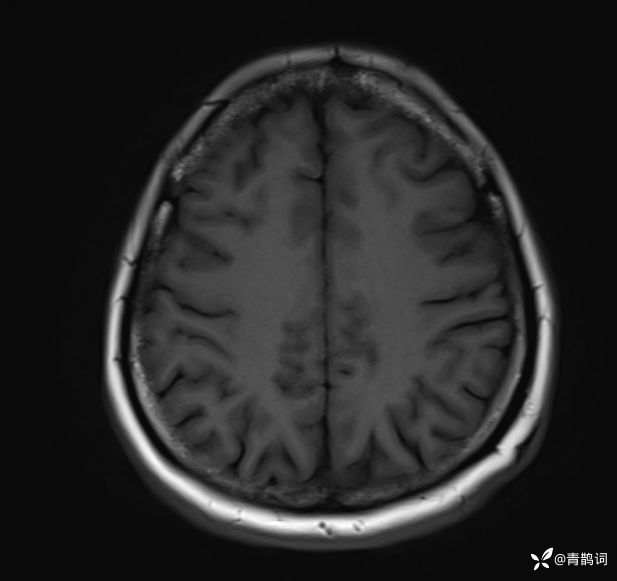

病例分享 | 45岁女患,7年的病史,结合影像学,如何诊断?

1、患者:女, 年龄:45岁

2、主诉:走路不稳渐加重7年,饮水呛咳伴头晕2年渐加重。

3、简要病史:患者于入院前7年出现走路不稳,表现为行走右偏,逐渐加重,易跌倒、不能自理;近2年出现饮水呛咳、吞咽困难及头晕;病程伴有耳鸣、反应迟钝,无恶心、呕吐。既往否认高血压、否认糖尿病、否认冠心病。

4、体格检查:体温36.0℃,脉搏80次/分,呼吸20次/分,血压140/70mmHg。查体:神清,构音障碍;眼球运动自如,双水平性眼震,左视时明显;双侧瞳孔等大同圆,左:右=3mm:3mm,对光反射灵敏;双侧额纹对称,双侧鼻唇沟对称;伸舌居中;四肢肌力4级,肌张力减低,四肢腱反射亢进,双侧Babinski征阳性;粗测感觉未见明显异常;四肢共济运动完成差,左侧为著;脑膜刺激征阴性。

入院后完善磁共振:

T2: